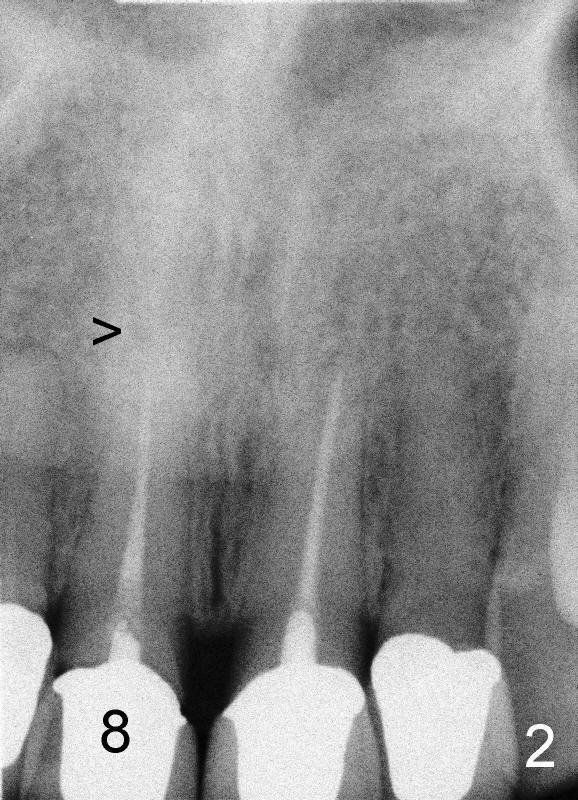

A 44-year-old lady has fractured #8 and agrees to have the tooth extracted after failure of recementation (Fig.1).  Pre-implantation X-ray shows minimal periapical radiolucency (Fig.2: >).  A 5x20 Tatum tapered implant is placed immediately after extraction (Fig.3: I).  Perio dressing is placed and a flipper is delivered.

Sixteen days after surgery, the patient returned with chief complaint "I do not have pain, but there is a swelling".  Exam shows that there is localized apical swelling with + fluctuance (Fig.4: *) and granulation tissue at gingival margin (>).  Under local anesthesia, I & D is performed with sanguine exudate, buccal apical plate perforation with implant threads exposed.  Tetracycline normal saline is used for irrigation.  The patient was asked to return every 1-2 days for irrigation.